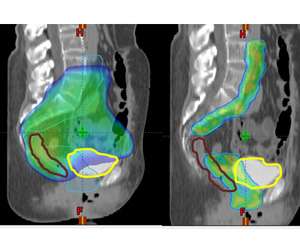

IMRT is a treatment advance that allows us to modulate the intensity of the radiation dose within a given radiation field. This means that the distribution of the radiation dose can be sculpted more finely around targets of interest while sparing more normal tissues. An example of this can be seen below where the axial CT image on the left is an example of a 3D-conformal plan and on the right is an example of an IMRT plan on the same patient. One can see that the IMRT plan allows the majority of the dose to be placed around the lymph nodes (which is the target) while sparing the bowel centrally.

Here at UCLA we have multiple state of the art radiation treatment machines that are capable of IMRT. These include: Tomotherapy, TrueBeam, NovalisTX, and ViewRay. Because the radiation dose is more sculpted with IMRT it is critical that the patient be set up properly each day. Image guidance (IGRT) is used to verify your position and anatomy prior to your treatment to ensure that the intended radiation targets are being treated properly. Any adjustments in your setup are made and then when 100% certainty is achieved the treatment is delivered.

The technology at UCLA was designed in conjunction with scientists in the Division of Medical Physics. UCLA is the first institution to deliver high precision, high resolution IMRT using the Novalis linear accelerator. The beam shaping device of the Novalis is equipped with 3 mm "leaves" as opposed to the standard 10 mm leaves of most other commercial devices.